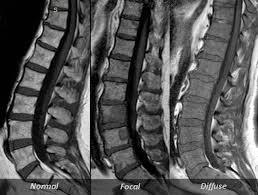

The Use Of Whole Body Mri In Multiple Myeloma Rcp Journals

The Use Of Whole Body Mri In Multiple Myeloma Rcp Journals from www.rcpjournals.org

Multiple myeloma is a cancer of plasma cells, which are white blood cells found mainly in the bone marrow. Find more information on clinical trials that are open for enrollment at mount sinai's center for excellence for multiple myeloma. Multiple myeloma (mm), also known as plasma cell myeloma and simply myeloma, is a cancer of plasma cells, a type of white blood cell that normally produces antibodies. Treatment response, detection of relapse. Related online courses on physioplus. 16,000 new cases and 11,000 deaths. Changing the treatment landscape for hematologic malignancies learn more. In multiple myeloma, when the cancer protein level is up, the normal antibody levels are down. If you still can't find it, please let us know so we can add it!. Tell the radiologist or the radiology technician about your diagnosis before receiving dye injection into. It accounts for approximately 10% of all. Other tests include blood monoclonal immunoglobulin and radiology tests to determine the extent of bone lesions. Spotlight revised international staging system for multiple myeloma: